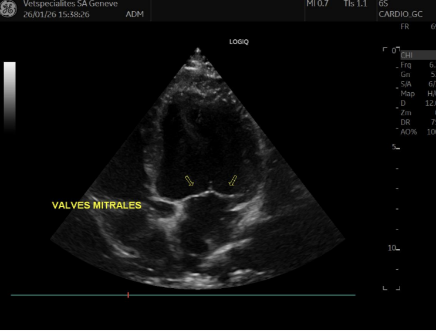

Les signes de la maladie mitrale sont visibles à l’échocardiographie, mais n’engendre aucun remodelage du cœur (seules les valves sont modifiées)

Les modifications des valves mitrales sont visibles à l’échocardiographie ET des signes de remodelage du cœur sont présents. Aucun symptôme clinique n’est encore présent

Différents stades de maladie myxomateuse mitrale ( Photo 1 : valve mitrale normale ; Photo 2 : prolapsus modéré, Photo 3 : prolapsus sévère)